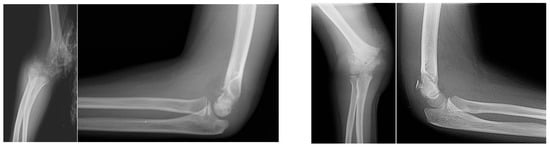

Figure 5. Final configuration of the fracture after reduction and percutaneous pinning, using two lateral wires and one medial wire. All wires were inserted with the elbow in extension. On the left is the AP view, and on the right the lateral view.

Pinning is carried out with the elbow in almost full extension (0–10 degrees of flexion) (Figure 4). Our preferred configuration is two lateral and one medial 1.6 mm K-wires. We prefer this configuration, as it has been shown to provide the biggest stability and has been recommended for the most unstable and comminuted fractures [3] (Figure 5). First, two lateral wires are inserted under fluoroscopy. Finally, the medial wire is placed. Insertion of the medial wire might be challenging due to medial swelling commonly accompanying this type of fracture. Several techniques have been described for medial wire placement, the most common being the mini-open technique (when small incision is made, exposing the medial epicondyle and making sure the ulnar nerve is not injured during wire insertion) [10]. Though the medial soft tissues are commonly compromised in this fracture subtype, making an open incision increases the insult to the already compromised soft tissues, thus potentially causing further complications. We prefer to insert the wire percutaneously. The elbow is kept in extension, thus keeping the ulnar nerve posterior to the medial epicondyle (the ulnar nerve has been described to occasionally move anterior to the medial epicondyle in flexion [14]). The wire is inserted percutaneously and gently, initially by hand next to and slightly anterior to the medial epicondyle under fluoroscopic control in two planes (AP and lateral), while the assistant observes for any motion at the fourth and fifth fingers which signaling irritation of the ulnar nerve. If movement of the fingers is observed, the wire is immediately repositioned. After an acceptable position is confirmed with fluoroscopy, the wire is advanced using a drill, keeping an eye on the 4th and 5th fingers. It should be noted that while we have not observed any iatrogenic injuries to the ulnar nerve resulting from our wire insertion technique in our cohort, due to the limited number of patients in the sideward displacement group, we cannot rule out the possibility that it happened only by chance, as ulnar nerve injuries after medial pinning have been described by other authors [15,16].